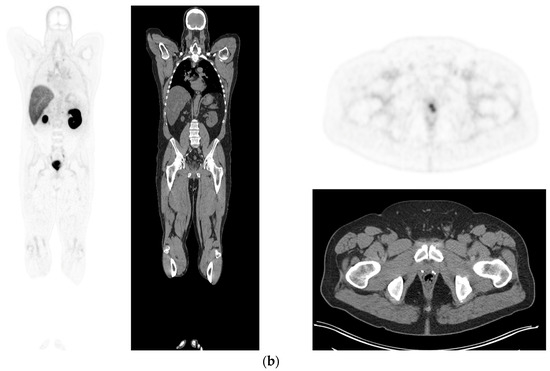

Figure 1.

PSMA PET-CT scan showing normal distribution of PSMA-11. 60 yr old M—Gleason 6 prostate cancer on active surveillance for past 2 years; PSA 7.2; MR imaging—low grade changes PIRADS 2. PSMA PET-CT: 68Ga-PSMA - 204 MBq; uptake 52 min; BMI = 29.7; Wt 90 Kg; coronal PET and corresponding CT slices (soft tissue windows) from left to right. (a)—physiological uptake in lacrimal, submandibular salivary glands, parotid glands, retropharyngeal soft tissue, liver, bowel, part of spleen and pooling of tracer in bladder; mild reactive tracer uptake in groin and axillary nodes. (b)—physiological uptake in head and neck; reactive uptake axillary nodes; focal uptake in apex of prostate gland anterior below the bladder SUV = 9.1; marked uptake/excretion of tracer in both kidneys.